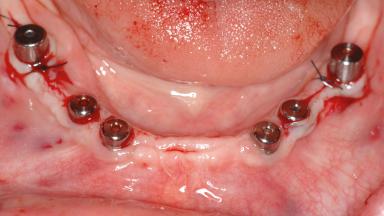

Area Full-Arch

# of Teeth All

# of Implants 14

Type of Implants Two-Piece

Bone Augmentation Horizontal|Sinus Floor Elevation|Staged|Vertical

Augmentation Materials Autogenous chips|Autogenous block(s)|Xenogenous|Membrane

Defining Characteristics Fully edentulous upper jaw to be rehabilitated with four or more implants

Modality Fixed hybrid bridge on 5+ implants